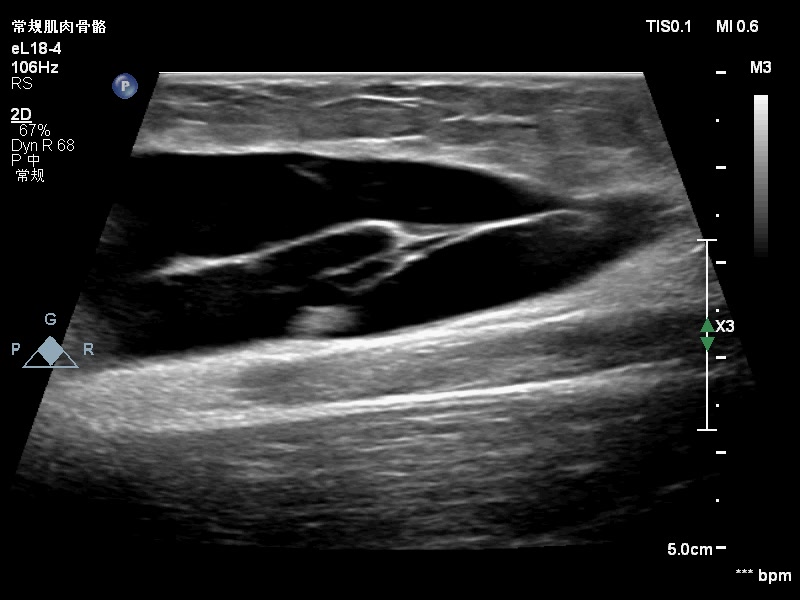

范特西_ 推荐男孩,12y,骑自行车过程中摔倒,右大腿内侧撞到了路边护栏,已有4-5天,今因大腿内侧肿胀就诊,声像图如下:

感觉是脂肪层和深方的深筋膜分离后积血。?所示应该是深筋膜吧。

大家考虑脱套伤吗?在报告中应怎么诊断?望各位老师指点。